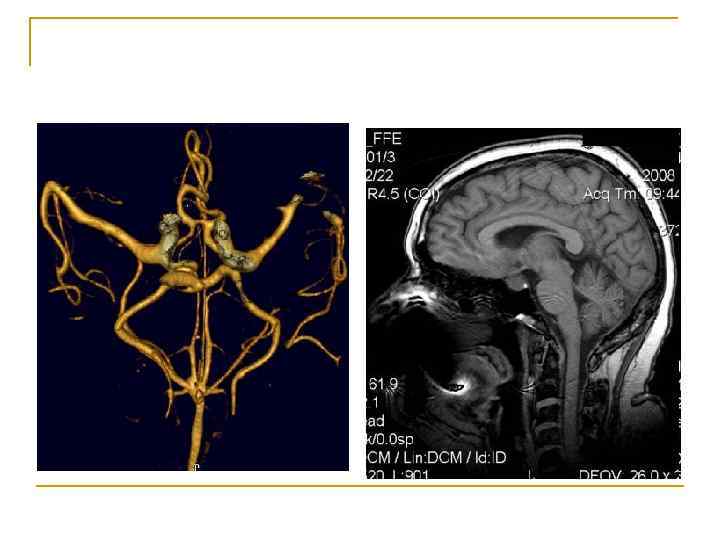

Вопрос 1. 4 Ангиография сосудов головного мозга Физиология человека Под редакцией В. М. Покровского, Г. Ф. Коротько Медицина, 2003 (2007) г. Страница 97 -98.

Ангиографическая установка фирмы «General Electric »

Вопрос 1. 6 Магнитно-резонансная нейротомография Физиология человека Под редакцией В. М. Покровского, Г. Ф. Коротько Медицина, 2003 (2007) г. Страница 97 -98.

Магнитно-резонансный томограф Signa MR/i фирмы «General Electric» 1 Тл

МРТ головного мозга